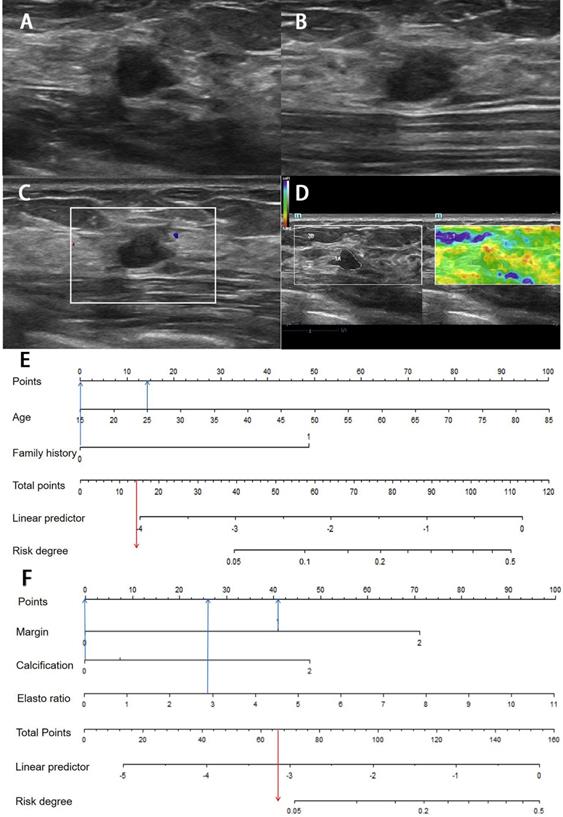

Images from a 54-year-old woman with a BI-RADS category 4a lesion in the left breast and the pathology was invasive ductal carcinoma. (A) Lesion size was 3.2*1.4 cm on B-mode imaging in the longest axis of the mass. The lesion showed unclear boundary. (B) The third measurement of the lesion from a view orthogonal to the first image. (C) Grade 1 in Colour Doppler. (D) The elastic ratio was 4.13 (blue represents soft and red represents hard). (E) In the clinical nomogram, the patient was high risk with 0.0735. (F) The lesion was classified as high risk in the ultrasound nomogram with a risk rate of 0.0634.

J Cancer Image

Figure 5

Image of a fibroadenoma in a 25-year-old woman with a BI-RADS category 4a lesion in the right breast. (A) Lesion size was 0.8*0.6 cm on B-mode imaging in the longest axis of the mass. The lesion showed indistinct margin. (B) The third measurement of the lesion from a view orthogonal to the first image is 0.7 cm. (C) Grade 0 in Colour Doppler. (D) The elastic ratio was 2.89 (blue represents soft and red represents hard). (E) In the clinical nomogram, the patient was classified as low risk with 0.0231. (F) The lesion was classified as low risk in the ultrasound nomogram with risk degree of 0.0434.

Figure 3

Ultrasound nomogram and its diagnostic value. A. Nomogram for assessing the risk degree based on ultrasonic-predicted factors. Draw a straight line up to the Points axis at the top to get the score associated with margin, calcification and strain ratio, and add the score of both covariates together and locate the total score on the Total points axis. Next, draw a line straight down to the “risk degree” axis at the bottom to obtain the probability. B. Receiver operating characteristic (ROC) curve for ultrasonic risk predicted model in both the development and validation cohorts. ROC curve of diagnostic performance for malignant lesions with AUC of 0.782 in the development group and 0.747 in the validation cohort.

The probability of ultrasound risk degree was obtained from the nomogram in the same method as above. The total points are calculated by adding all the points obtained from margin, calcification morphology, and strain ratio and the cut-off of risk degree was 0.0486. Patients were regarded “ultrasound high risk” with risk degree more than or equal to 0.0486, and “ultrasound low risk” with risk degree less than 0.0486.

In the development and validation cohorts, the discrimination of ultrasound risk nomogram was moderate with AUC of 0.782 (P = 0.905) and 0.747 (P = 0.359), respectively (Figure 3B). In addition, the Hosmer-Lemeshow test was not significant.